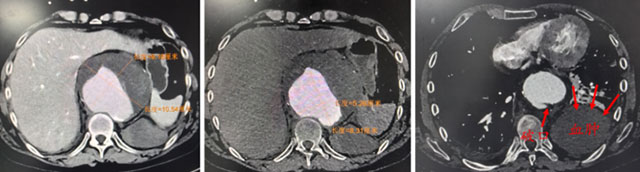

3月1日,在西南医科大学附属中医医院完善相关检查后发现,王先生病情已经十分凶险,胸主动脉瘤破裂,已形成腹膜后血肿,且瘤体累及腹腔干动脉、肠系膜上动脉及双肾动脉,合并感染,随时有生命危险,救治难度极高。

明确治疗方案后,介入·血管科团队在全麻下为王先生实施了主动脉腔内隔绝术,并同步完成腹腔干动脉、肠系膜上动脉及双肾动脉支架植入血管重建术。

团队历时8小时,成功隔绝动脉瘤,重建内脏动脉血供。术后,王先生转入CCU接受严密监护与精细护理。在多学科团队的持续协作下,生命体征逐步稳定,感染得到有效控制,脏器功能恢复良好,顺利出院。